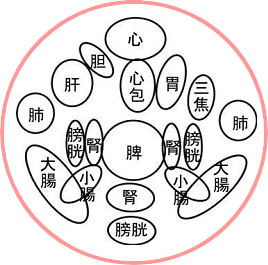

| HOME > 学習ノート> >お腹のみかた、触れ方② 腹診は先人たちのご苦労されて残されたものから、多くを学ぶことができます。 たにぐち書店の難経からお腹の経絡図をお借りして載せています。 ツボも細かく書かれていますが、お腹にはすべての経絡が関わっています。 肺経は経絡図を見ますと、表面上では胸部の一部と腕だけだと思われますが、決してそうではなく腹部の中に 入って働いていることが右の図をご覧頂くとお判り頂けるかと存じます。   また、お腹のみかたも、鍼道秘訣集、夢分の描かれたものや増永静人先生の腹部スジ反応部位をご覧頂くと、 人により観方、感じ方が異なっていることが分かるかと思います。 ではどちらを信じて学べば良いのでしょうか。 どちらの方もこの道の大家でいらっしゃいますから迷うでしょう。 答えですが、まず、どちらも覚え、頭の片隅に入れておきますが、最終的には幾度も施術をしながら自分の感覚 を信じ、答えを出すことです。 鍼道秘訣集 夢分

増永静人 経絡図